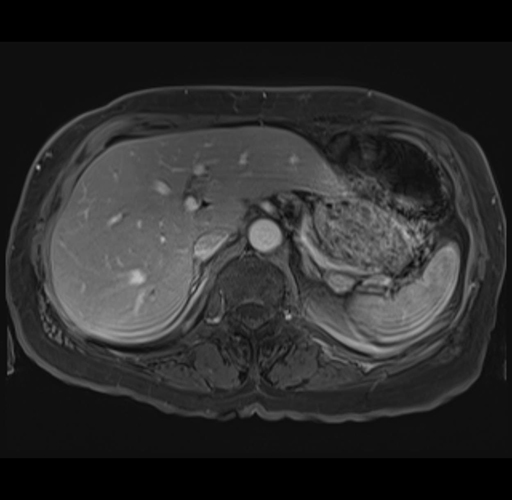

MRI T1